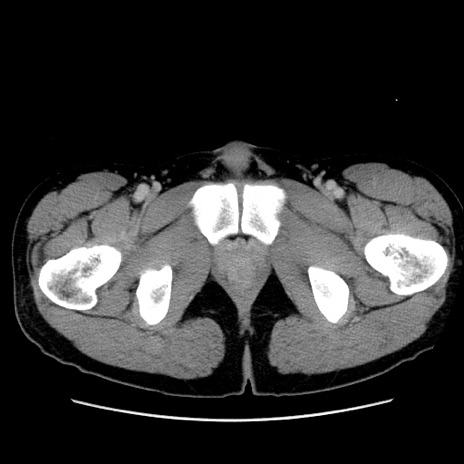

症例36(横断像)

【症例】20歳代 男性

【主訴】心窩部痛

【現病歴】今朝より上腹部痛あり。一旦軽快していたが再度出現したため救急要請。昨日夕に白身の魚を含む刺身を食べた。

【身体所見】BP 136/89mmHg、HR 74/min、BT 37.0℃、腹部:膨満、軟、心窩部に圧痛あり。反跳痛なし、筋性防御なし、腸雑音やや亢進あり。

【データ】WBC 17700、CRP 0.48